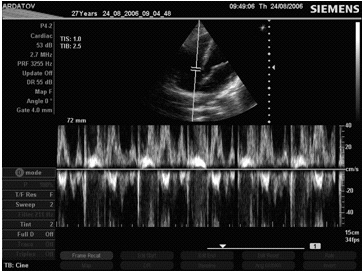

При М-модальном сканировании видно, что движение нормального митрального клапана отражает все фазы диастолического наполнения левого желудочка (рис. 1). Во время систолы желудочков (интервал С-Д) весь клапан смещается вперед из-за движения в этом направлении митрального кольца. В фазу быстрого наполнения передняя створка открывается с достаточно большой скоростью и движется вверх к датчику (интервал Д-Е). В середине диастолы, во время медленного наполнения левого желудочка и повышения в нем давления, створка клапана прикрывается, удаляясь от датчика (интервал Е-F). В систолу предсердий она снова быстро открывается (F-А) и с началом его систолы вновь закрывается (А-С). Таким образом, форма движения передней створки митрального клапана во время диастолы напоминает букву М. Задняя митральная створка совершает подобное движение в противоположном направлении, но с меньшей амплитудой, и по своей форме напоминает букву W. Нередко при открытом клапане она сливается с нижележащими структурами и не всегда четко лоцируется.

Рис. 2. М-эхограмма нормального митрального клапана (собственное наблюдение).